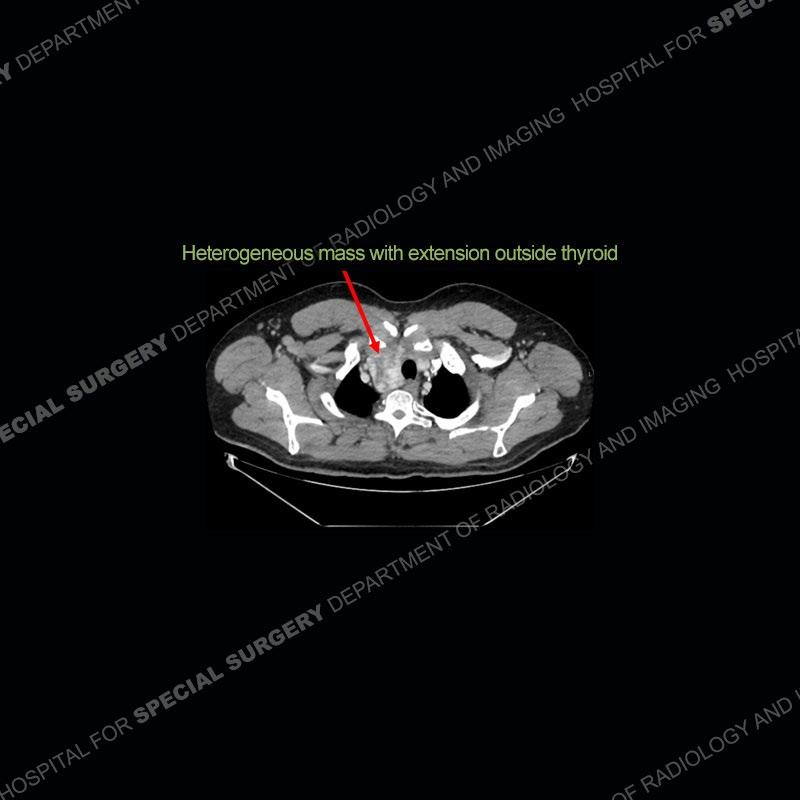

Findings

The chest radiographs demonstrate a leftward deviation of the trachea. CT images demonstrate a large, somewhat heterogeneous mass of the thyroid that extends outside the confines of the thyroid tissue. There is a subtle, enhancing soft tissue mass of the proximal right humerus. Slightly prominent mediastinal lymph nodes are present with additionally, multiple supraclavicular lymph nodes.

Over the years we have shown a couple of these cases which may be considered more so an “eye test” then anything else. In clinical practice, these are often very difficult cases as the initial finding of the tracheal deviation may be easily overlooked. Screening radiographs are clearly most often used to assess cardiopulmonary function before induction of anesthesia but at times other findings of great and unfortunately grave consequence can be found. The evaluation of the incidental thyroid mass on CT and MRI is an ever changing situation. Parameters such as age of patient, extension outside of the thyroid, enhancing nodules, and local invasion of lymph nodes are evaluated to see if a lesion needs to be further evaluated.

Although not strictly a part of the evaluation of an “incidental” thyroid lesion, evaluation of the adjacent lymph nodes and bony structures can also be quite important. In this case, there is an enhancing mass of the right humerus. This is very subtle and can only really be recognized by evaluating the density of the bone. Typicaly marrow will have a fatty density or nearly fluid density. As the density, as in this case, approaches soft tissue an infiltrative process must be entertained. Thyroid mets are markedly vascular accounting for the areas of enhancement of the humeral mass. The mediastinal and supraclavicular lymph nodes although not individually enlarged, should raise suspicion of an underlying inflammatory/neoplastic process.